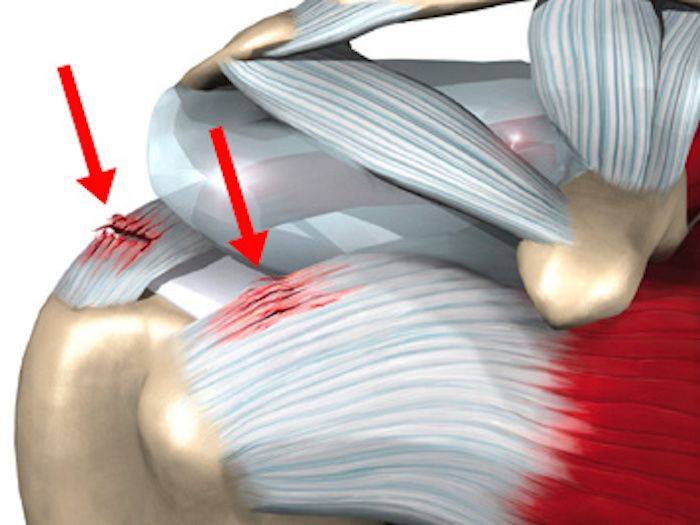

Фотографии мышц ротаторной манжеты плеча